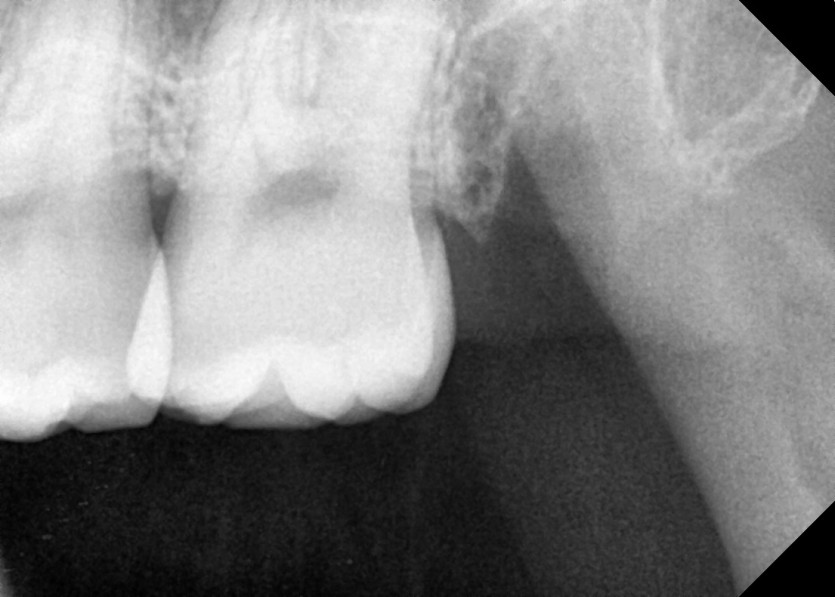

#28,38 사랑니 발치

구강 외과 전문의가 당일 발치했습니다.